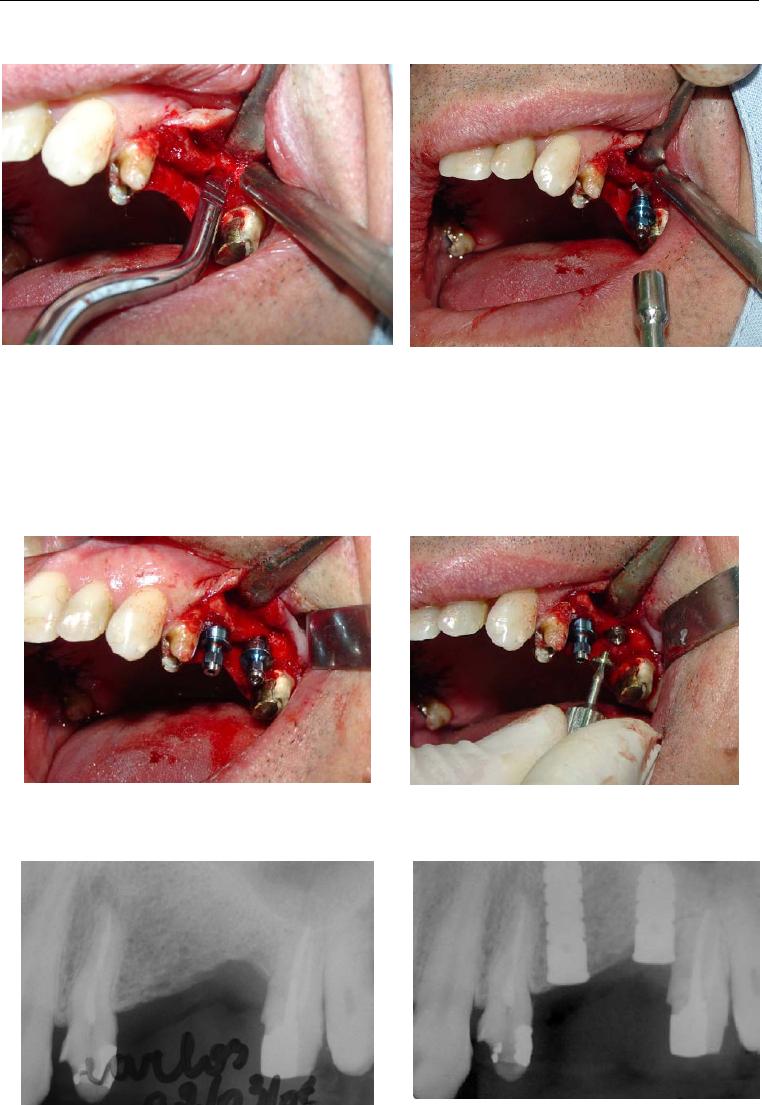

Foi no intuito de transpor estas dificuldades que se idealizou o sistema de

implante inicialmente conhecido como Wedge (figura 1) e que, após dez anos de